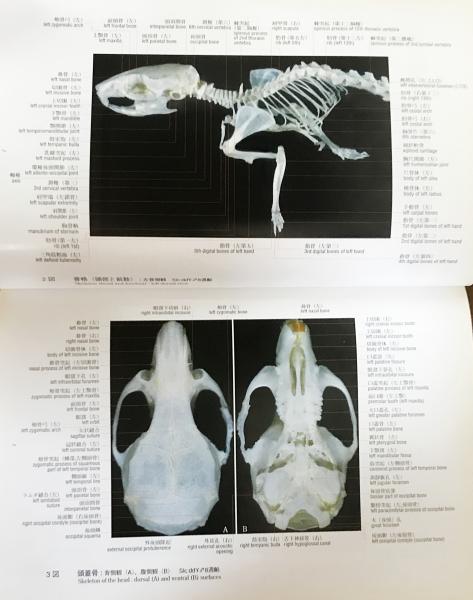

ラットの断面解剖アトラス。ラットの断面解剖アトラス - メルカリ。ラットの断面解剖アトラス。熊本県産ヒノヒカリ 30kg。 B 中古品としては綺麗と判断した商品。一般中古よりは状態の良い商品。 C 中古品として一般的な状態の商品。やや使用感があり、日焼けやキズなどがみられる場合がある商品。 D 中古品と考えても、気になる汚れやキズなどがある商品。。[A12303631]陽性・陰性症状評価尺度(PANSS)マニュアル。暫間ミニインプラント療法/永田睦(著者)。[A11078446]新生児学テキスト [単行本(ソフトカバー)] 一般社団法人 日本新生児成育医学会。改訂版・神経内科のスピード学習と専門医学習/泉義雄,五十棲一男【著】。[A12335451]徹底討論! ハートバルブ・カンファレンス。Ea-080/化学両方の領域 2016年4月号 Vol.32No.4 医薬ジャーナル社 2016年3月25日発行 特集:食の安全と微生物汚染 医療 医学 薬学/L1/61121。シノプティック・マテリア・メディカ 4訂/F.ヴァーミューラン(著者),RAH著(著者)。8K0098◆連続写真と動画で学ぶ 白内障手術パーフェクトマスター 基本から難症例への対処法まで 谷口重雄 ▽。[A01906937]すぐわかる小児の画像診断 改訂第2版 (画像診断別冊KEYBOOKシリーズ) [単行本] 荒木 力、 原 裕子; 野坂 俊介。IVR-手技,合併症とその対策 Interventional/石橋忠司(著者),山田章吾(著者)。眼光学 1 眼内レンズ/市川宏(著者)。[A11048022]造血器腫瘍アトラス 形態、免疫、染色体から分子細胞治療へ 谷脇 雅史、 横田 昇平; 黒田 純也。カラー図解 脳神経ペディア 「解剖」と「機能」が見える・つながる事典/渡辺雅彦(著者)。培養細胞実験ハンドブック 改訂 基本から最新の幹細胞培養法まで完全網羅!/黒木登志夫(著者),許南浩(著者)。[A01564935]病院の世紀の理論。機能性食品の作用と安全性百科/上野川修一(著者)。[A01351009]ICUブック 第4版。整形外科スタンダード手術基本手技/山本眞(著者)。H19-047 醫學博士 茂木藏之助 著 茂木外科總論 南山堂 書き込みあり。。胃 形態とその機能 第2版 形態とその機能/川井啓市(著者)。[A12326342]リウマチ・膠原病アトラス 廣畑 俊成。日経デジタルヘルス年鑑(2017)/日経デジタルヘルス。[A12090911]硬膜動静脈瘻塞栓術ハンドブック [単行本] 滝 和郎。[A11248770]一歩進んだ麻酔管理~常識は常に真実か?~ 国沢 卓之。[A12333909]睡眠とてんかん: その密接な関連性。[A12335621]バスキュラーアクセスのトラブルシューティング ─ 電子版付 ─。[A12344518]改訂第6版 救急診療指針 上巻 (上巻)。ネッター解剖学図譜 第2版/相磯貞和(著者)。[A01204523]EBMによる糖尿病経口薬の選択と適正使用。【まとめ/訳あり】緑内障 11冊セット 眼科/診療/薬物治療/ガイドブック/【2211-041】。[A12325943]不整脈 識る・診る・治す (循環器内科専門医バイブル) [単行本] 平尾見三; 小室一成。[A11760723]領域横断的がん取扱い規約。[A12325147]イラストでイメージする 小児の心エコー 第2版 (第2版)。眼科手術学/ゲオルク・アイスナー(著者),渡辺郁緒(著者)。[A12309814]診断と治療2019年増刊号。[A12357725]頭頸部がん手術ノート 輪層の外科。[A11067697]CTパターンから理解する呼吸器疾患: 所見×患者情報から導く鑑別と治療 門田 淳一。★カラーフォト皮膚病1★籏野 倫★。胸部CTの異常陰影/松原義人(著者)。[A12301703]オルソケラトロジ-・ハンドブック トッド・D.ウィンクラ-、 ロジャ-・T.ケイム; 日本オルソケラトロジ-協会。[A12343460]小児画像診断の勘ドコロNEO。DVD SPAT 頚椎・胸椎編/鹿島田忠史(著者)。[A11550186]腸疾患診療―プロセスとノウハウ。和蘭薬鏡(全) 科学書院。脳神経外科臨床マニュアル 改訂第5版/端和夫(編者),三國信啓(編者)。[A11185929]脊椎・骨盤の外傷手技のコツ&トラブルシューティング [DVD付] (OS NOW Instruction)